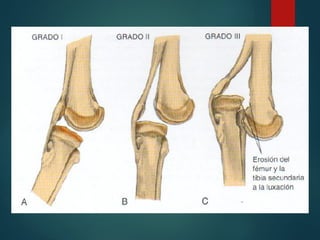

Clasificación de

Langrnskiöld

Deformidad de Blount Alteración del eje de la extremidad inferior producto de una tibia vara proximal  Producto del cierre precoz de la fisis proximal medial  Puede ser uni o bilateral

 1937 –Blount - “osteocondrosis deformans tibiae” - Descripción de deformidades características - Identifica formas precoz y tardía  1964 – Langrnskiöld - diseña sistema de clasificación y pronostico

fisiopatología  Alteraciones dela porción medial de la fisis tibial proximal.  Inhibición relativa de la porción posteromedial del cartilago de crecimiento: - Varo - Antecurvatum - Rotación interna

• 66.

Clínica  Habitualmente asintomático Ex Físico - Genu varo exacerbado al pararse en un pie - Prominencia palpable en borde medial de la metáfisis proximal de la tibia - Torsión tibia interna - Bilateral 50%

• 67.

 Distorsión epifisio– fisio – metafisiaria (patognomónico)

tratamiento  Ortopedico Menores de3 años - Tipos 1 y 2 Ferulas - Eficacia no bien determinada - Buen resultado aparentemente en unilaterales - Malos resultados en obesos y bilaterales - Duración 2 años

Quirugico - > 3años - Estadios 3,4,5,6 (<3años) - Falla de tratamiento ortopedico Alternativas -osteotomía Epifisiodesis Modulación del crecimiento